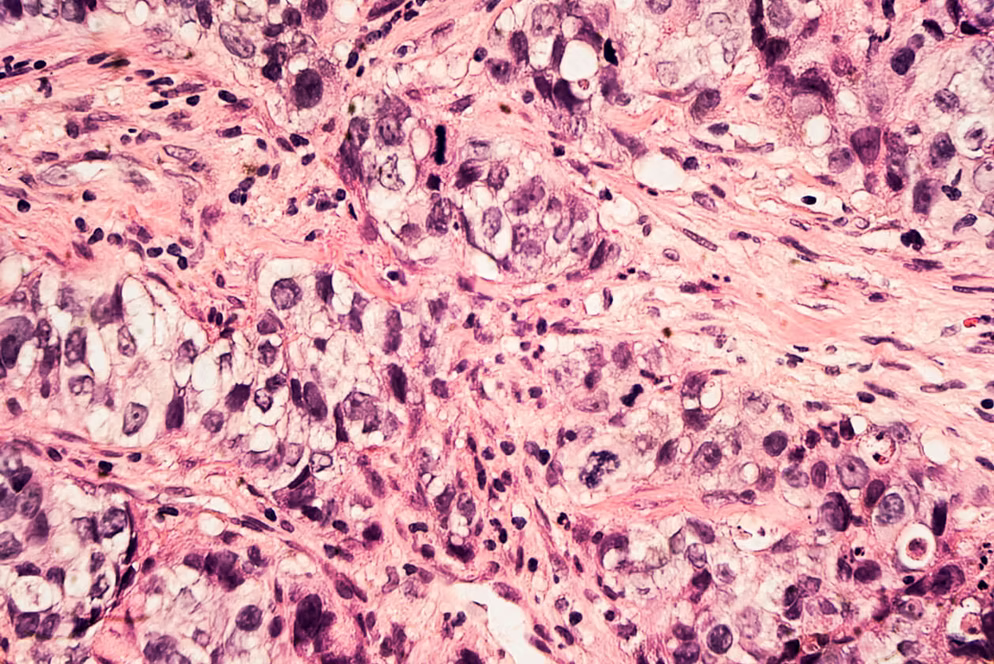

💗 علاج سرطان الثدي في تركيا

يُعَدّ سرطان الثدي من أكثر أنواع السرطان شيوعًا بين النساء، ولكن بفضل التشخيص المبكر وخيارات العلاج الحديثة، ترتفع معدلات الشفاء عامًا بعد عام.